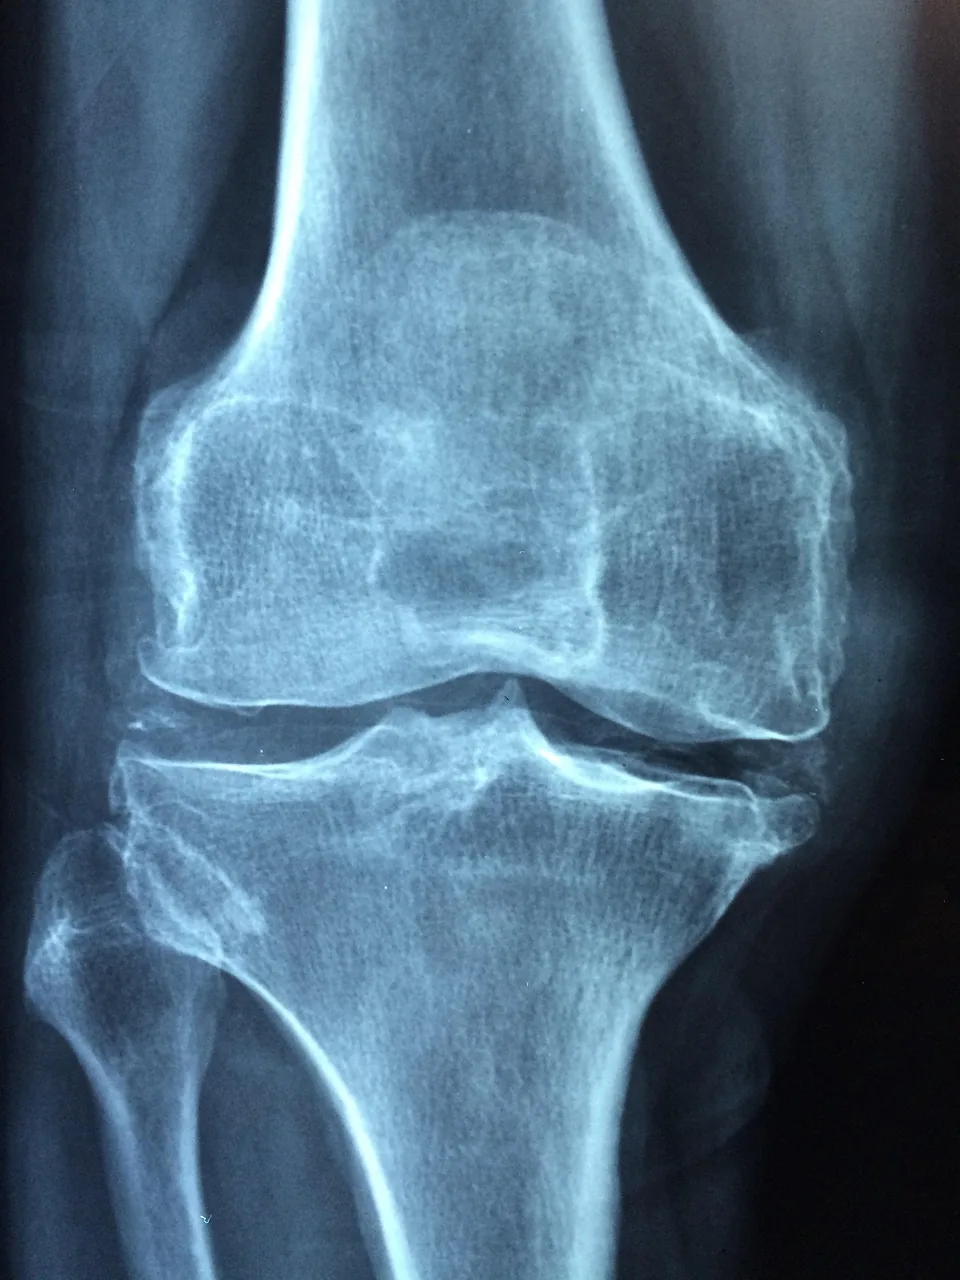

- 퇴행성 관절염 (골관절염) – 나이, 반복 사용, 과체중 등이 연골 마모를 일으켜 통증과 염증을 유발합니다.

- 전문가 진료 및 검사

정형외과에서 병력 청취, 신체 진찰 후 X선, MRI, 관절경 등을 통해 조직 손상 유무를 확인합니다. - 약물 치료 및 주사 요법